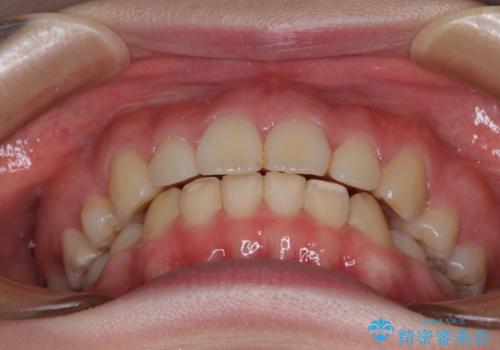

- 口元の突出感を気にして来院された患者様です。

上下左右の第一小臼歯4本を抜歯して口元を下げる治療計画としました。

非常に大きな虫歯のあった下顎大臼歯は、根管治療を行い、矯正治療後にオールセラミッククラウンにて補綴治療を行いました。

当初予定では3年以上かかるとお伝えしておりましたが、スムーズに歯列が整い、2年強で終了することができました。